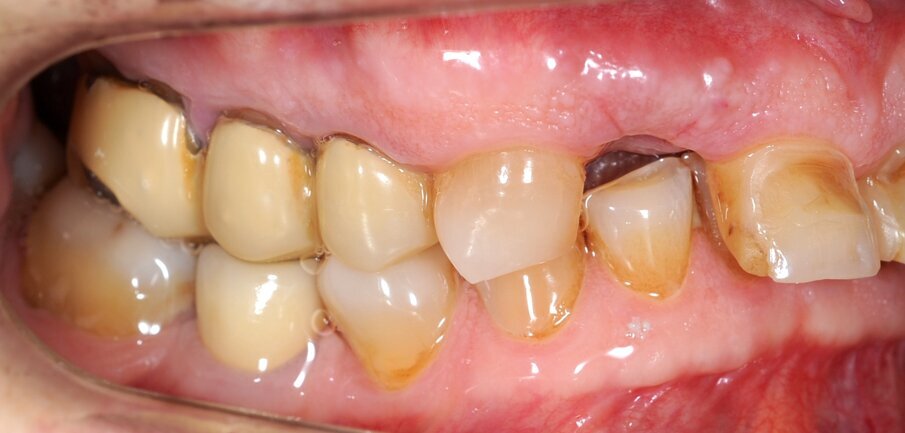

Un paziente di 66 anni, con anamnesi patologica di NIDDM ben compensato e cardio-vasculopatia ischemica in buon compenso farmacologico, si presenta alla nostra attenzione per ascesso parodontale alla radice residua del dente 1.2 e per multiple fratture dei manufatti protesici esistenti (Figg. 1-6). È evidente la presenza di grave malocclusione con perdita di VDO, usure e fratture dei restauri protesici e dei denti residui, presenza di abfractions cervicali. Il paziente evidenzia alla visita modesta dolenzia muscolare alla palpazione, specie a carico dei muscoli pterigoidei mediali e temporali, apertura della bocca ridotta e lieve rumorosità delle TMJ.

L’infezione a carico della radice del dente 1.2 è immediatamente attribuibile a frattura verticale con sondaggio positivo di 9 mm (Fig. 7). Estratta la radice di 1.2 fratturata, il paziente richiede una riabilitazione protesica fissa all’arcata superiore che preveda il minor numero possibile di interventi endodontici e chirurgici. Viene da noi proposta una riabilitazione protesica full arch che consenta, previo studio del caso gnatologico e terapia interlocutoria con provvisori in PMMA, la definizione di un’occlusione a funzione sequenziale in TRP per l’aumento controllato della VDO e la stabilizzazione dei rapporti articolari, ora visibilmente compromessi.